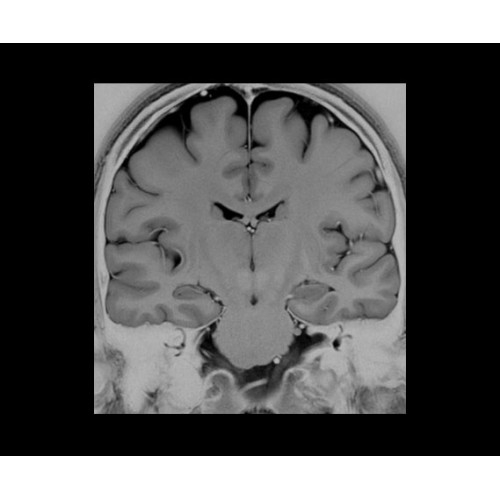

SIGNA Architect 3.0T — это новейший МРТ аппарат компании GE, который предлагает высочайший уровень производительности — в системе 128 приемных каналов, 48 канальная катушка головы, полный спектр клинических возможностей. Высокий уровень комфорта пациента обеспечивают такие особенности как отсоединяемый стол, положение пациента «ногами вперед» для всех видов исследований, SilentWorks — бесшумное и MAGIC — быстрое сканирование.

Теперь возможности МРТ поражают еще больше благодаря ультрасовременным решениям для визуализации с SIGNA Architect 3.0 Тл, объединяющей новейшие достижения в области МР-технологий и интуитивно понятный интерфейс. Система SIGNA Architect, разработанная на базе новой платформы SIGNA Works, представляет собой гармоничное сочетание дизайна и функциональности. Каждый элемент системы направлен на повышение производительности, эффективности клинической практики, финансовых показателей, а также комфорта и безопасности пациента.

Поле обзора 50x50x50 см и апертура шириной 70 см позволят достоверно визуализировать сложные анатомические области для пациентов с крупным телосложением, например, плечи и бедра. Феноменальная однородность системы SIGNA Architect обеспечивает наиболее широкое поле обзора с улучшенными характеристиками градиентов. Ничто не останется незамеченным.

• NeuroWorks — универсальное решение для визуализации анатомии головного мозга, позвоночника, сосудов и периферических нервов с четкой дифференциацией тканей.